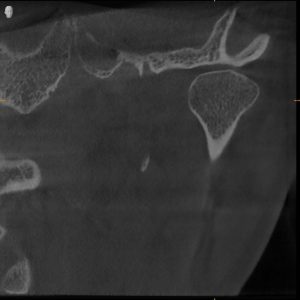

MRI Findings:

- Bilateral disc displacement without reduction

- This explained everything — the pain, the restriction, the dysfunction